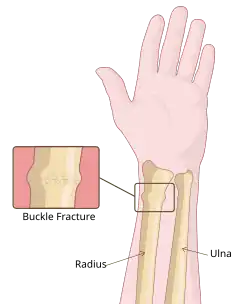

A Torus fracture, also known as a buckle fracture is the most common fracture in children.[1] It is a common occurrence following a fall, as the wrist absorbs most of the impact and compresses the bony cortex on one side and remains intact on the other, creating a bulging effect.[2] As the bulge is only on one side of the bone, this injury can be classified as an incomplete fracture. The compressive force is provided by the trabeculae and is longitudinal to the axis of the long bone, meaning that the fracture itself is orthogonal to that axis.[3] The word "torus" originates from the Latin word "protuberance."[4]

Torus fractures are low risk and may cause acute pain. As the bone buckles (or crushes), instead of breaking, they are a stable injury as there is no displacement of the bone.[5] This mechanism is analogous to the crumple zones in cars. As with other fractures, the site of fracture may be tender to touch and cause a sharp pain if pressure is exerted on the injured area.

Physical activities or sports such as bike riding or climbing increase the associated risk for buckle fractures in the potential event of a collision or fall. As aforementioned, the most common buckle fracture is of the distal radius in the forearm, which typically originates from a Fall Onto an Outstretched Hand (FOOSH).[6] Such orthopaedic injuries are distinctive in children as their bones are softer and in a dynamic state of bone growth and development, with a higher collagen to bone ratio so incomplete fractures such as the buckle fracture are a more common occurrence.[7]

- The buckling of cortical bone, which may appear as a small bulge or protuberance in the radius or ulna.